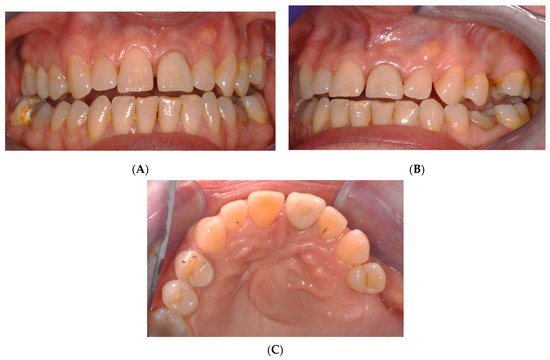

2.1. Chief Complaints History and Clinical Findings

2.2. Delivery of Treatment